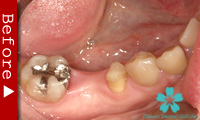

歯のない部分が広い場合

臼歯が失われた場合、従来は取り外し式の部分入れ歯で咬合機能を回復させてきました。

これに対し、インプラントなら天然歯と同様の感覚の”固定式”人工歯を入れることができます。